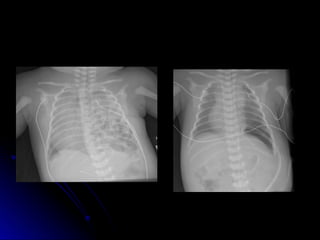

Congenital lobar emphysema

 Lesions that cause air trapping, with

Lesions that cause air trapping, with

compression of surrounding tissue

 Most common in left upper, right middle

Most common in left upper, right middle

and right upper lobes

 Usually attempt low volume ventilation.

Usually attempt low volume ventilation.

Sometimes selective intubation of other

bronchus

 May require surgical resection

May require surgical resection